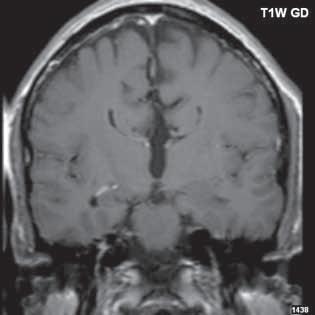

Roztroušená skleróza (RS) 189

II 1 1